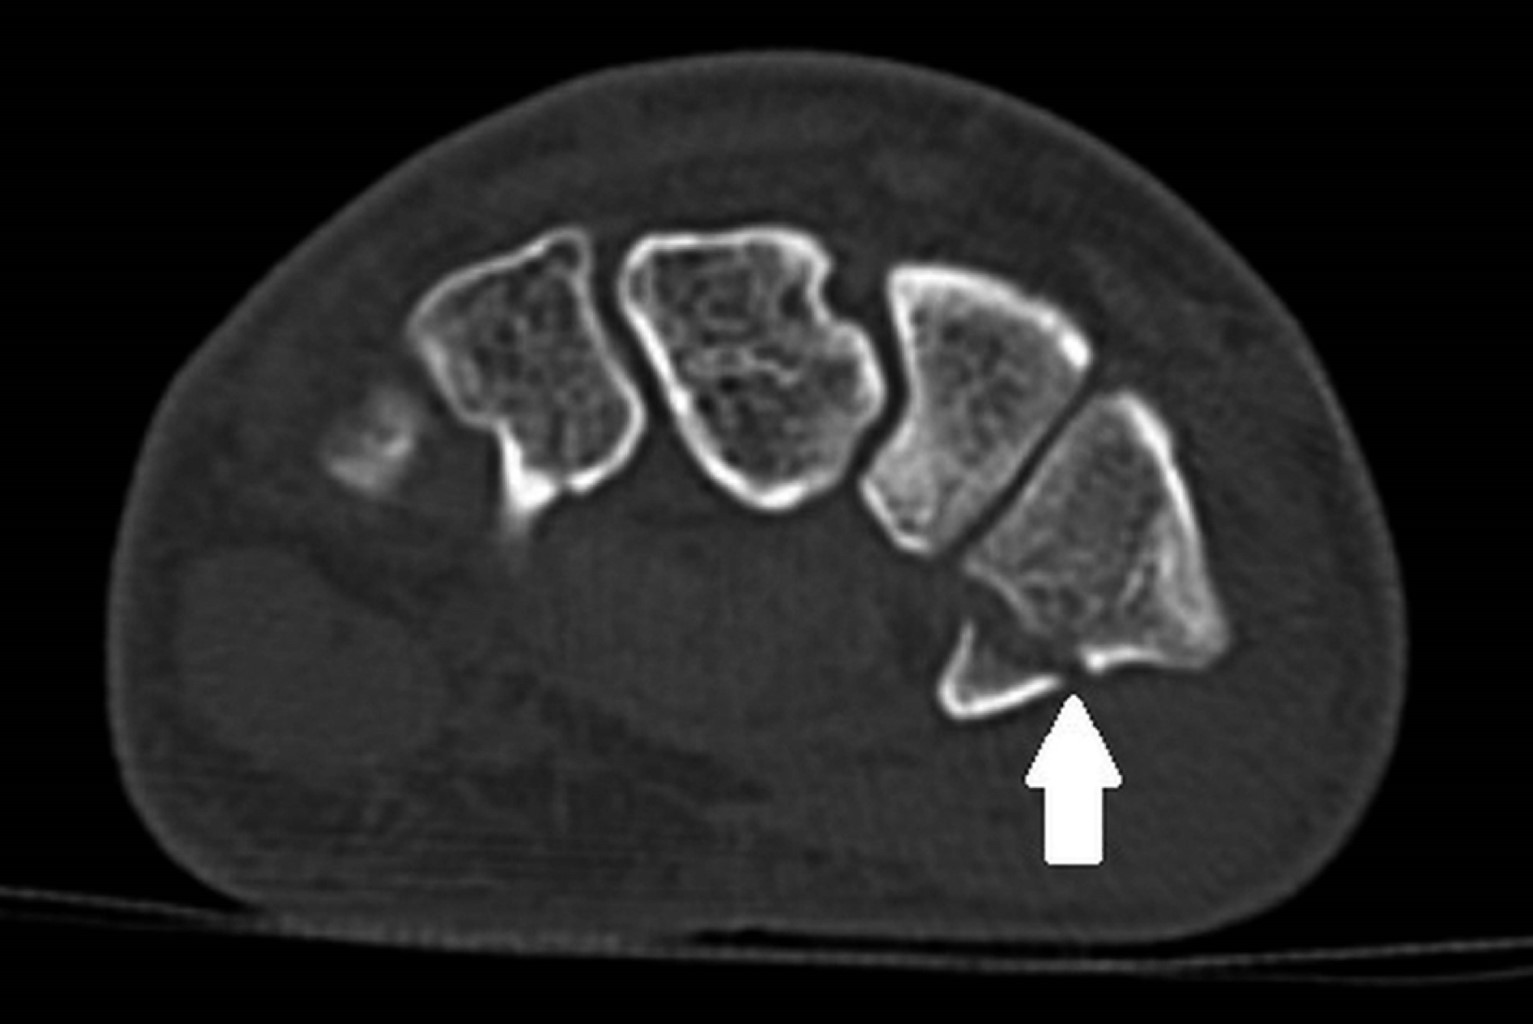

Computed tomography (CT) scan reveals a hamate bone fracture without apparent misalignment (Figure 1) and a type I trapezium tuberosity base fracture (according to Walker's classification) with a 0.2 cm fragment distance, without significant misalignment [ICD 10-S62] (Figures 2 and 3).

Figure 1